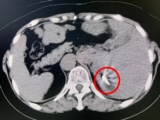

术前影像

病灶 毗邻心脏

60岁的胡女士因结肠癌于2023年1月接受了肝左外叶切除+右半结肠切除+肝右叶肿瘤切除手术,2023年12月复查时发现肝脏出现新的占位,考虑为术后肝内多发转移,一处病灶靠近心脏位置,另外一处病灶靠近肾脏,如若再次手术,不仅创伤大,而且对术后病人的康复不利,胡女士慕名来到我院介入科,团队通过仔细评估并组织讨论,与胡女士及家属充分沟通,决定采用“复合式冷热消融术”创新治疗方法。